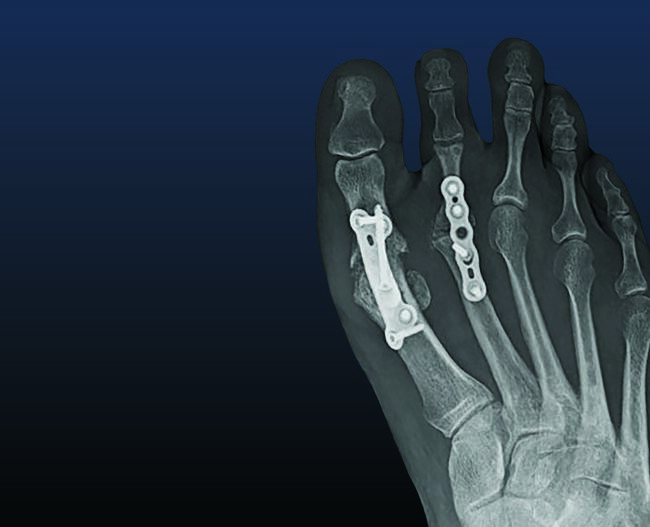

Implant Arthroplasty. Synthetic implants are a well-known treatment option to preserve motion in the first MPJ; however, there are limited reports of hemiarthroplasty or total MPJ replacement implants utilized in the lesser MPJ. Descriptions of replacement arthroplasty with silicone,11 ceramic,14 and titanium15 devices all exist. Implant arthroplasty provides patients with an option to decrease pain and retain motion at the MPJ; however, literature has not reported reliable success. Complications include prosthesis failure, loosening, synovitis, osteolysis, and increased potential for revision surgery.16 The senior author prefers a metatarsal head resurfacing implant as a primary “go-to” procedure for advanced arthritis of the second MPJ (see second photo set above). Our preferred implant system has a screw/post that lends immediate stability to the implant. Also, it does not require altering the weight-bearing surface of the metatarsal bone, which lessens the chance of developing postoperative transfer metatarsalgia.